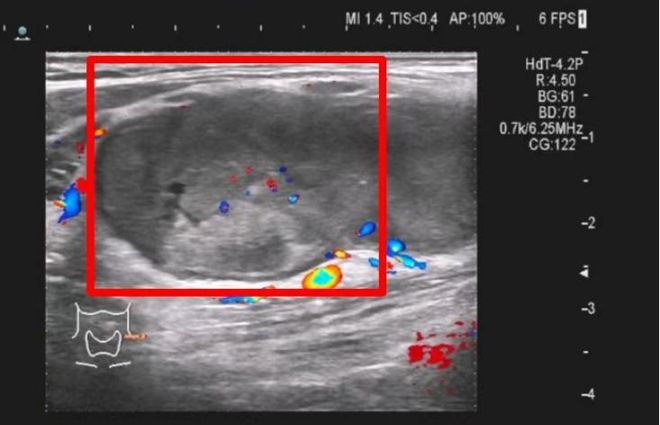

甲状腺超声检查图像:左叶多个结节,大者4.6×3.7×3.6cm,部分结节融合状。